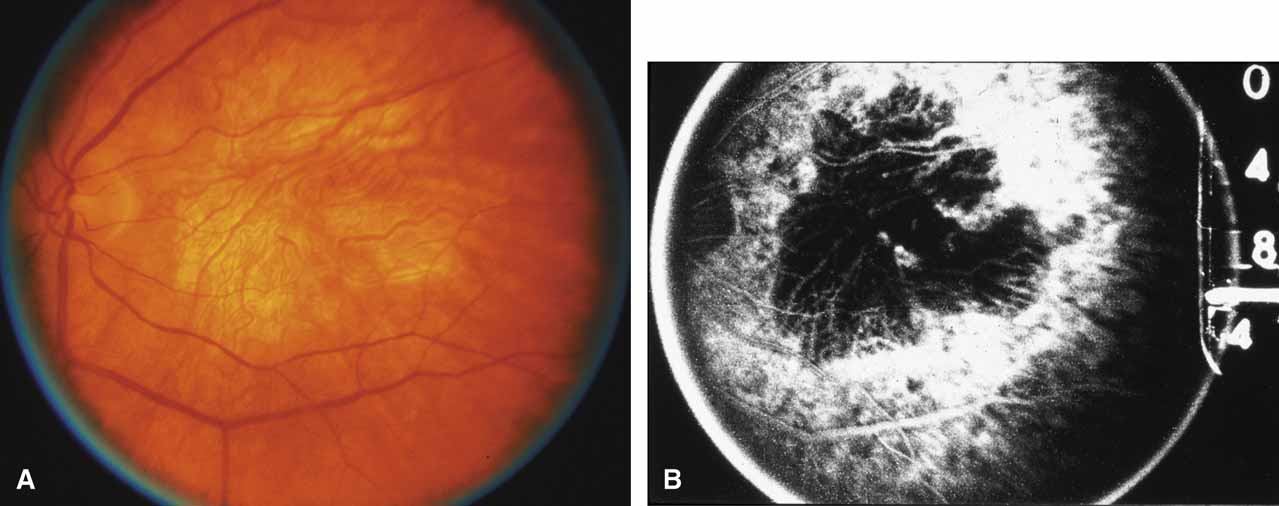

First described by Nettleship12 in 1884, central areolar choroidal dystrophy (CACD) (MIM No. 215500, Phenotype catalog number (MIM) from McKusick VA: Mendelian Inheritance in Man. Catalogs of Human Genes and Genetic Disorders. 12th ed. Baltimore: Johns Hopkins University Press, 1998 [http://www.ncbi.nlm.nih.gov/Omim/]), as it is most appropriately called,13 has been described under many names, including central areolar choroidal sclerosis, central areolar choroidal atrophy, central angiosclerosis, and central senile choroiditis.14,15 The disorder can be autosomal dominant or autosomal recessive, and phenocopies can occur from many other diseases, including mutations of peripherin/RDS16–19 and advanced stages of macular dystrophies (see later text). A locus for CACD has been identified on chromosome 17p.20 The earliest symptoms result from pericentral scotomas and include difficulty reading, poor dark adaptation, reduced visual acuity, and glare sensitivity. The earliest fundus findings are subtle and include pigment epithelial and choriocapillaris lesions in the macula (Fig. 1A) that enlarge and eventually form the punched-out central atrophic lesions typical of this disease (Fig. 1B). Histopathology shows fibrotic scarring with absence of choriocapillaris, retinal pigment epithelium, and overlying photoreceptors in the affected areas.21 The Ganzfeld electroretinogram is usually normal early in the course but may become mildly to moderately abnormal for cone and rod responses late in the course of disease when extensive atrophy of the choroid and secondarily the pigment epithelium and neurosensory retina occurs. Recent studies using the multifocal ERG have indicated that the abnormality of retinal function extends beyond the borders of the visible atrophy and is consistent with presynaptic photoreceptor dysfunction.22 The EOG can be normal or mildly abnormal depending on the extent of associated retinal pigment epithelial dysfunction.

Other forms of central choroidal dystrophy exist that do not show the discrete oval lesions of typical central areolar choroidal sclerosis. These forms of central choroidal choriocapillaris atrophy often present with progressive pigment epithelial mottling and patchy choriocapillaris atrophy initially limited to the macula (Figs. 2A and 2B). With time, the atrophy enlarges and eventually encompasses the entire posterior pole (Fig. 2C). For this form of central choroidal atrophy, a gradual transition usually occurs from atrophic central pigment epithelium and choriocapillaris to essentially normal retina and choroid in the peripheral fundus.